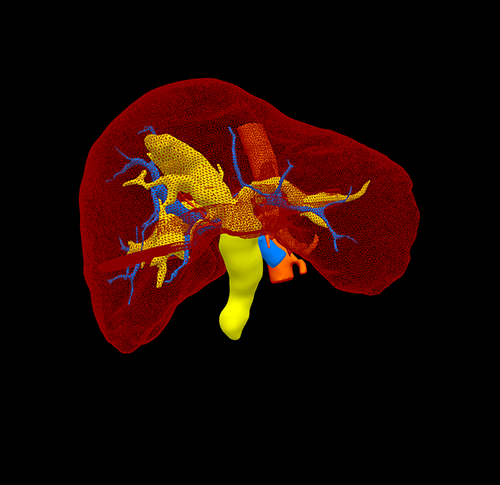

右肝胆管结石,胆总管结石---右半肝切除、T管引流